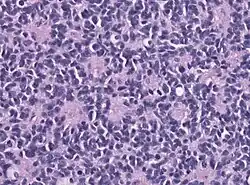

Макроскопически медуллобластомы представляют собой мягкий узел серовато-розового цвета, который чётко отграничен от окружающей ткани. Микроскопически опухоль состоит из густо расположенных недифференцированных клеток, которые образуют своеобразные структуры в виде правильных или беспорядочных рядов, которые сравнивают с «грядами» и «колоннами»[4].

Для гистологического строения медуллобластом характерны структуры в виде «розеток», образованных кольцевидно расположенными опухолевыми клетками, отростки которых сходятся в центре розетки. Опухолевые клетки обладают повышенной митотической активностью. Наряду с гиперхромными округлыми ядрами в клетках медуллобластом также встречаются овальные и вытянуто-овальные, удлинённые, а также более крупные светлые ядра с чётким ядрышком[4].

Строма опухоли содержит небольшое количество мелких, тонкостенных сосудов. Очаги некроза и кисты для медуллобластом не типичны. Рост новообразования инфильтративный с прорастанием прилежащей ткани и мягкой оболочки мозга[4].